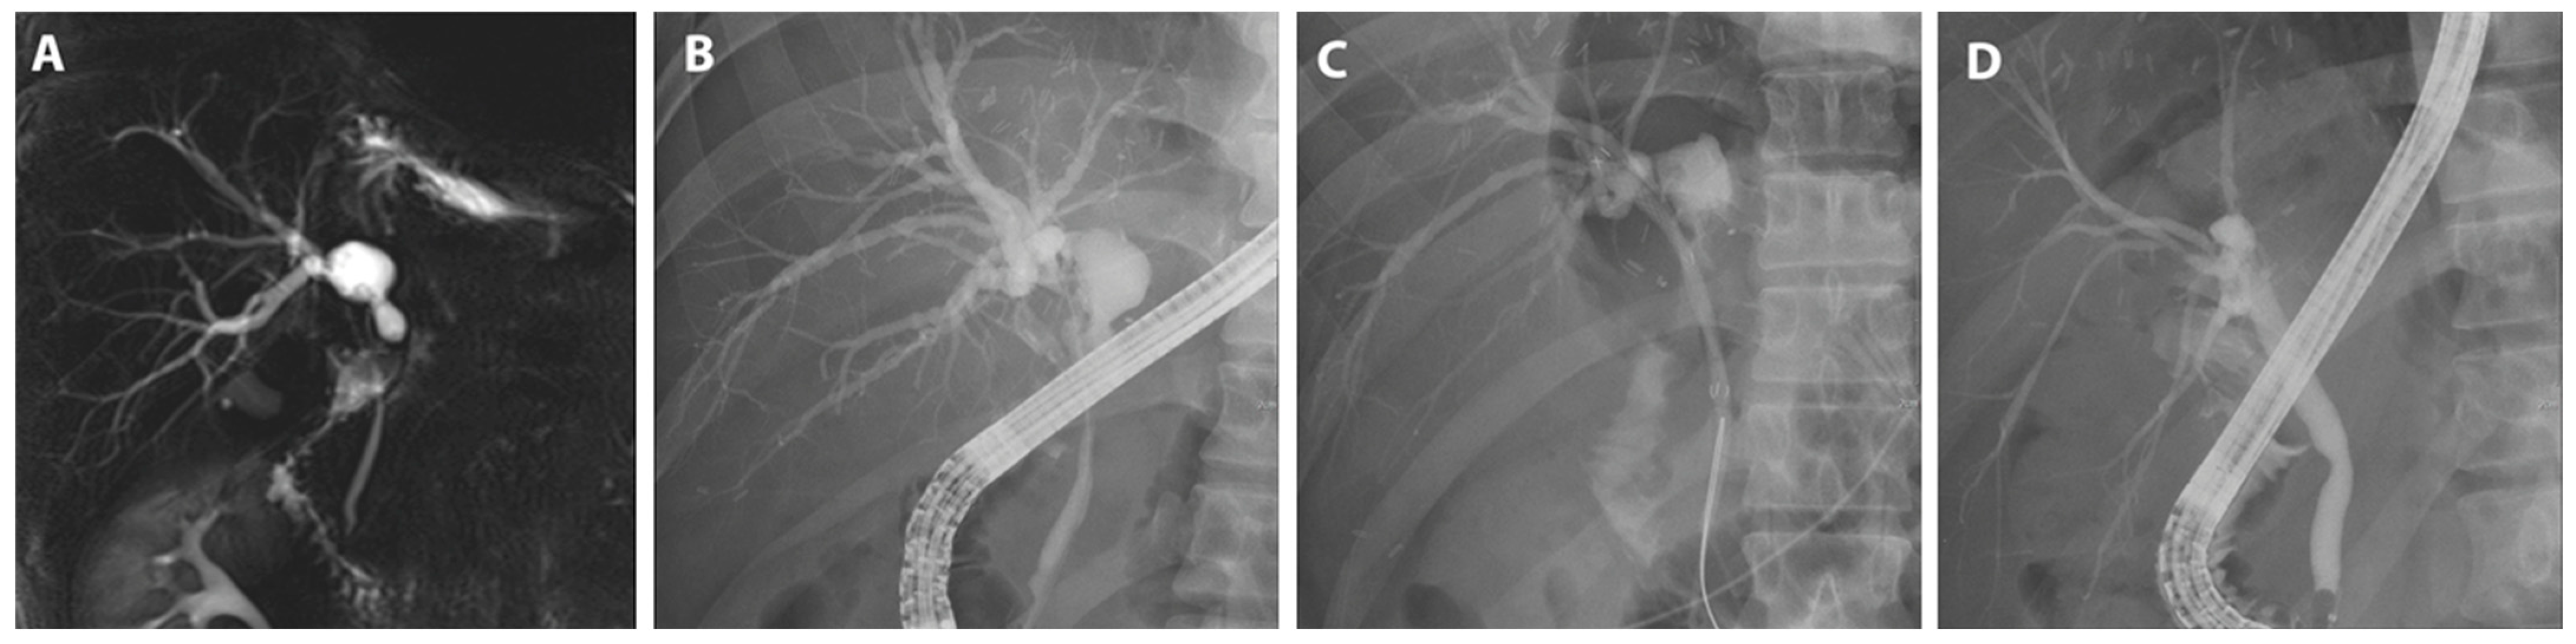

A patient subjected to hemi-hepatectomy developed a hilar stricture that was treated using FCSEMS; additionally, a plastic stent was prophylactically deployed in another bile duct to prevent cholangitis (Figure 4).

Figure 4.

FCSEMS treatment of biliary anastomotic stricture after liver resection. A case diagnosed with biliary anastomotic stricture after left hemihepatectomy for liver donation and treated with FCSEMSs is presented. (A) Magnetic resonance cholangiopancreatography shows segmental narrowing at the hilar and common hepatic duct with mild central intrahepatic bile duct dilatation, and a 2 cm-sized biloma was observed at the resection margin. (B) A hilar stricture was observed on cholangiogram. (C) An FCSEMS (6 mm in diameter, 5 cm in length; KAFFES) was deployed at the site of biliary anastomotic stenosis, with a plastic stent placed prophylactically, as expansion of the FCSEMS could narrow the adjacent branches. (D) After the FCSEMS was in use for 6 months, including one replacement, the stent was removed, and the procedure was terminated after confirming that the biliary anastomotic stricture was resolved.